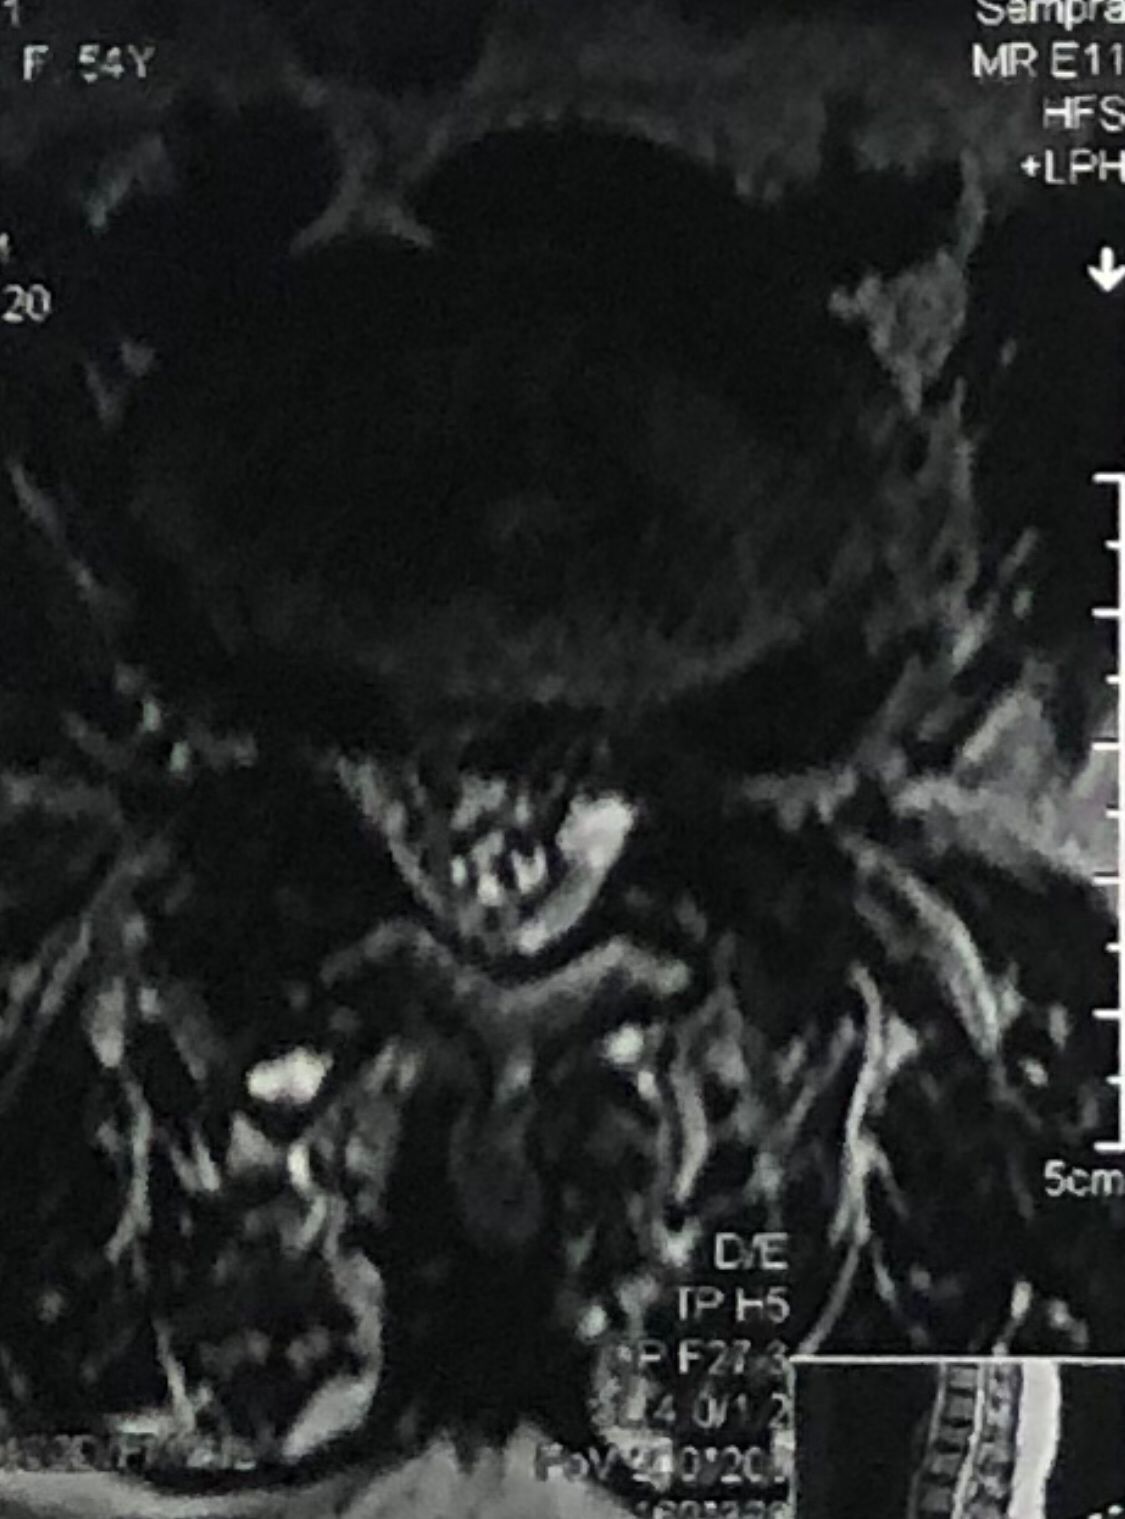

46 years old female patient presented to my clinic yesterday june 1/2025 with LBP and radicular L leg pain for several months which hasn’t responded to physio 2 neurosurgeons have visited her and didn’t suggest any surgery Neurological exam was unremarkable please see her mri/ emg/ncv and her huge tarlov cyst and possible L IVF L4-5 hyperbulge I ordered sacrum mri and ct scan and new emg/ncv and asked her with her sacral Ct scan and MRI first sees another two famous neurosurgeons and see if that large cyst is the reason for her pain if not i can work on her L4-S1 area Do you think her radicular pain can originate from her large cyst in sacrum? Do you consider surgery and removing her sacral cyst?